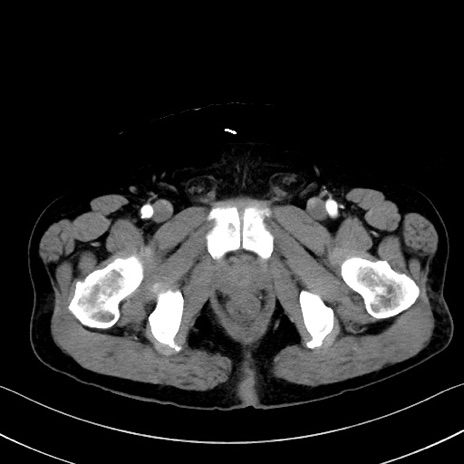

症例35(横断像)

【症例】70歳代 男性

【主訴】腹部膨満、嘔吐

【現病歴】昨日より腹部膨満感出現。本日増悪し、仙痛出現。嘔吐あり、受診。

【既往歴】糖尿病、胆摘後

【身体所見】BP 149/80mmHg、HR 74/min、BT 35.9℃、腹部:膨満、軟、圧痛なし。腸雑音減弱あり。上腹部正中切開瘢痕あり。

【データ】WBC 13500、CRP 1.72